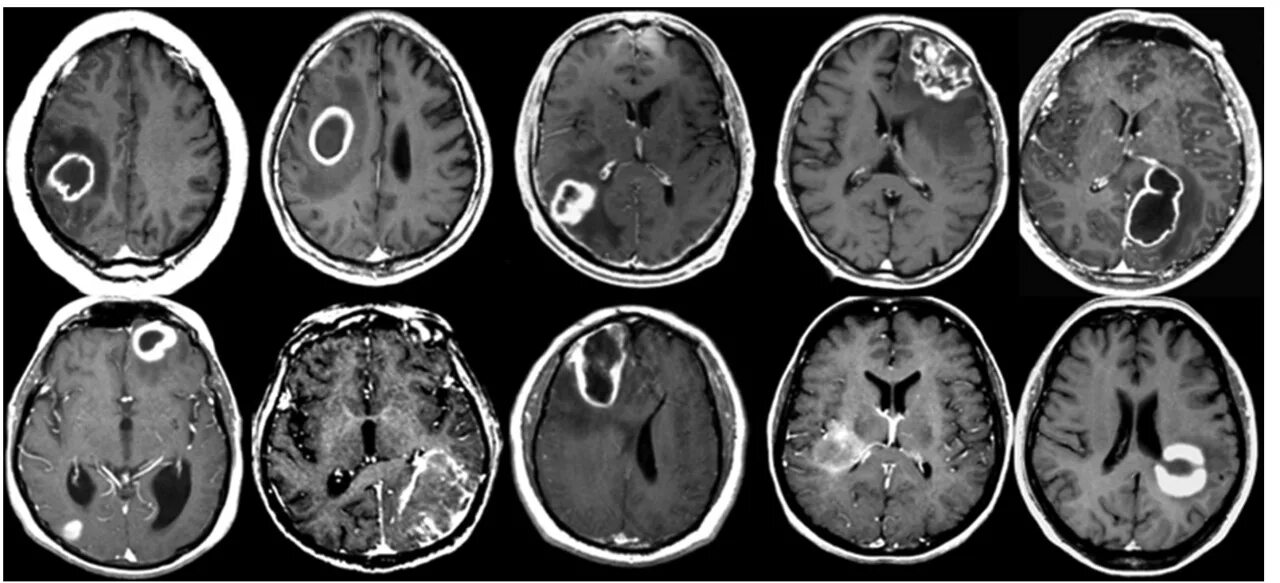

Метастазы головного мозга кт